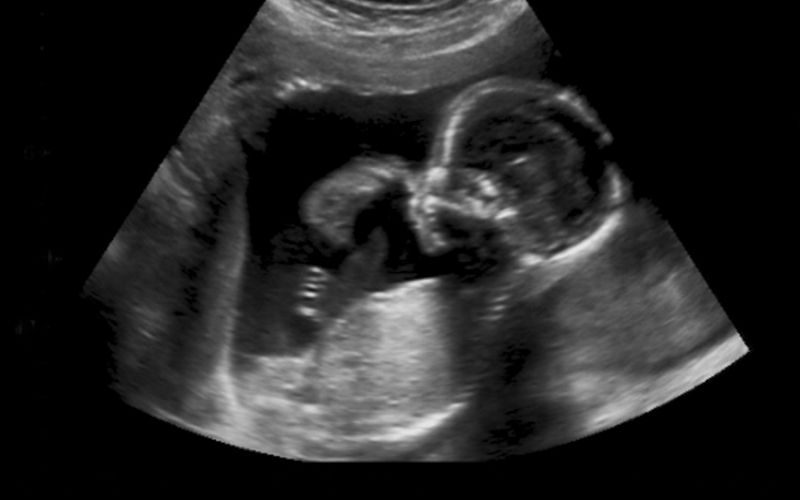

Siêu âm khảo sát dị tật hình thái là kỹ thuật siêu âm chuyên sâu, tập trung đánh giá hình thái và cấu trúc các cơ quan của thai nhi trong giai đoạn thai đã phát triển tương đối hoàn chỉnh.

Bác sĩ sẽ quan sát chi tiết não bộ, tim, phổi, cột sống, tay chân, khuôn mặt, thành bụng, hệ tiêu hoá và hệ tiết niệu của thai nhi nhằm phát hiện sớm các dấu hiệu bất thường.

Siêu âm khảo sát dị tật hình thái thường được chỉ định vào tuần thai 18 – 22. Đây là thời điểm các cơ quan của thai nhi đã hình thành tương đối hoàn chỉnh, đủ lớn để bác sĩ quan sát rõ cấu trúc và phát hiện sớm những bất thường nếu có.

Bác sĩ sử dụng máy siêu âm hiện đại để quan sát thai nhi ở nhiều mặt cắt, đánh giá chi tiết hình thái các cơ quan như não, tim, cột sống, ổ bụng, tay chân…